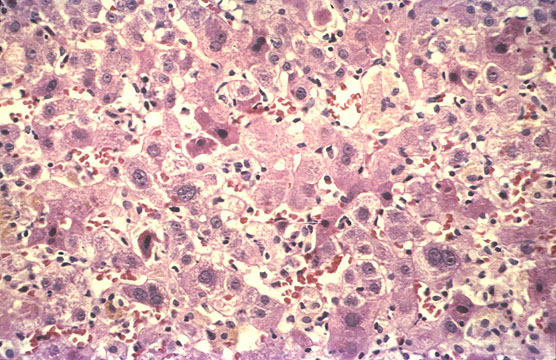

Confluent necrosis

Fig 91 - CONFLUENT NECROSIS: Death of adjacent groups of hepatocyte throughout the lobule. Confluence of many spotty necroses. Notice glycogen (red granules) depletion on damaged hepatocyte..